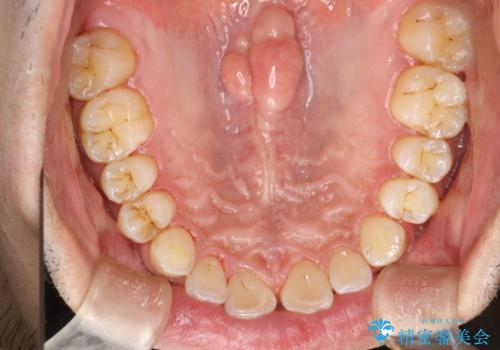

歯と歯の間の着色をPMTCでできる限り除去

- 歯と歯の間の着色を綺麗にしたいとのことで来院されました。PMTC60分で取れる範囲の着色や歯石などの除去を行いました。

毎日丁寧に歯磨きをしていても、日常生活での飲食物などにより着色してしまうことはあります。PMTCでは、歯の表面の凸凹にミネラルを補給して、ツルツルの表面に仕上げます